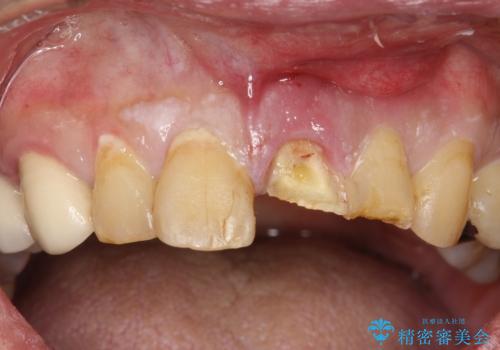

- 前歯のかぶせものの付け根が黒いところを気にされて来院されました。

以前メタルボンド(金属の裏打ちがあるセラミック)を入れたところが、歯肉退縮もあり、金属が見えてきている状態でした。

右上2は根管治療が途中のままになっていたようで、前歯3本の根管治療をしてかぶせものを新しくしていく治療計画を立てました。